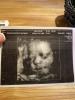

Куда сегодня сходить на 3Д УЗИ девочке? Посоветуйте хорошего доктора, если в СШУ нет мест!

Девочки посоветуйте пожалуйста к какому доктору сходить на 3д узи ,надо сегодня, в сшу сегодня нет мест уже

стикер